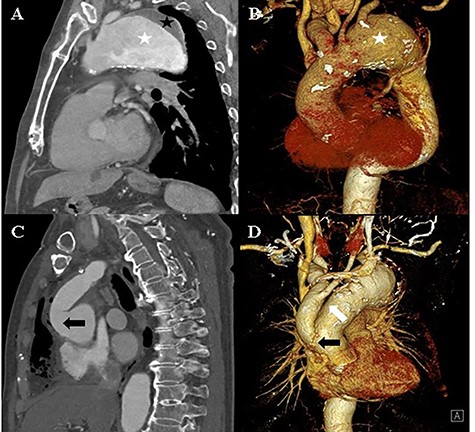

The TEVAR was performed 14 days after the debranching surgery. Under local anaesthesia, a Safari wire was placed in the left ventricle cavity. A Medtronic Valiant Thoracic Stent Graft (46 mm × 46 mm × 200 mm) was implanted in the ascending thoracic aorta and aortic arch, and a second Medtronic Valiant Thoracic Stent Graft (42 mm × 42 mm × 200 mm) was implanted in the aortic arch and descending thoracic aorta. The left subclavian artery was plugged with an Amplatzer Vascular Plug (16 mm) (Fig. 2).

A: Aortic angiography during TEVAR shows the thoracic graft implanted in the ascending thoracic aorta and aortic arch (white asterisk) and the thoracic graft implanted in the aortic arch and descending thoracic aorta (black asterisk). B: Computed tomography of the post-TEVAR shows the placed thoracic graft (white arrow). C and D: Computed tomography of the post-TEVAR shows the intimal dissecting flap at the proximal ascending aorta.